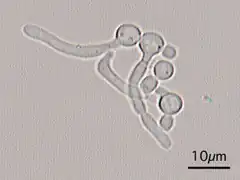

Germ tubes of Candida albicans -